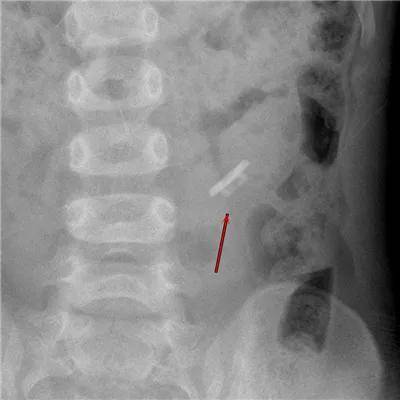

10岁·膝盖异物

半截针

患儿10天前不慎受伤,致半截床套针刺入右膝,无明显疼痛及活动障碍,至当地医院就诊摄片示右膝异物。